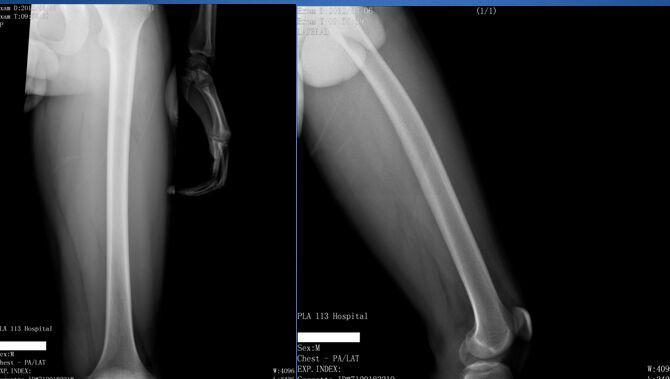

MRI6551:大腿MRI.二周后结果公布.

男,19岁,发现左大腿远端前内侧肿块一年.查体:左大腿膝上前内侧可触及一个大小约为3*6cm肿块,质中,活动差,有压痛.实验检查(-).

病理结果:肌间血管瘤,伴血栓形成。

病理结果:肌间血管瘤,伴血栓形成.

考虑 左大腿内侧软组织恶性肿瘤,脂肪肉瘤可能性大。

病变内见T1、T2低信号,说明有含铁血红素沉积或钙化,病变靠近关节囊,考虑膝关节色素沉着绒毛结节性滑膜炎。

考虑为血管瘤